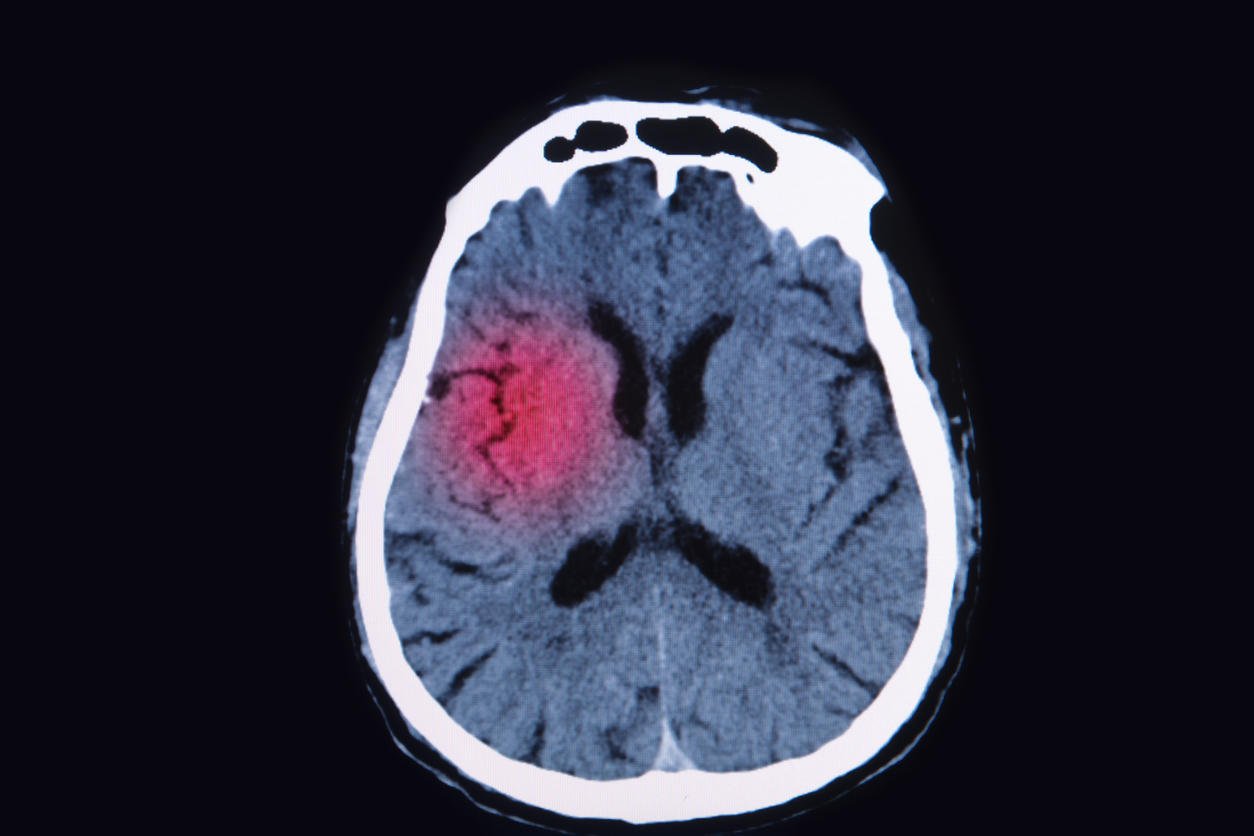

image par résonance magnétique (irm) du cerveau montrent une lésion cérébrale

Istock